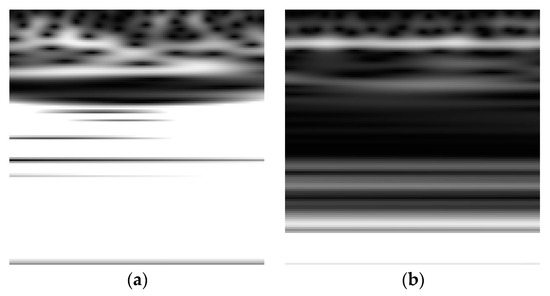

Shaban has also developed a deep learning framework based on three 13-layer ANN models applied on the Oz, P8, and FC2 channels of a 32-channel resting state EEG dataset for 15 PD subjects and 16 controls [29]. The framework achieved a testing accuracy, sensitivity, and specificity of 98%, 97%, and 100%, respectively, for distinguishing subjects with PD from HC when a majority voting scheme was applied on the prediction of the models. In addition, Shaban et al. have recently used a Wavelet-based CNN approach where a 20-layer CNN structure was applied directly to the Morlet wavelet transform [30,31] and the second-order derivative of the wavelet transform [32] of a resting-state EEG time-series with an accuracy, sensitivity, and specificity of up to 99.9% achieved at CP5 in order to classify subjects into PD patients or controls. Figure 6 shows an example of the Scalogram for a resting-state EEG signal captured for a healthy control and PD subject where the horizontal dimension represents time and the vertical dimension represent scale (i.e., reciprocal of Fourier frequency).

Figure 6.

Scalogram for an EEG signal captured for (a) a healthy control (b) a PD subject.

As shown in Figure 6, the values of the scalogram for the EEG related to PD exhibits relatively lower intensities as compared with the health controls’ EEG scalogram especially at the mid and high scales [30,31]. Table 1 presents a summary of the machine and deep learning techniques used to exploit the EEG dataset modality for PD along with the objective and the aim, performance, and limitations of the methods.